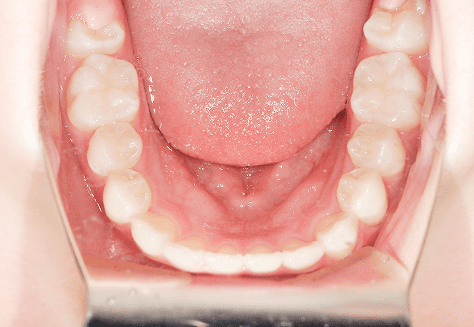

M.M

治療前

治療後

主訴

上下前歯4本が反対になっていてずっと気になっていた。

診断

右側第一大臼歯埋伏・反対咬合

年齢/性別

30代/男性

抜歯部位

非抜歯

使用装置

上下インビザライン

保定装置

上下ビベラリテーナー

料金

初回資料採得・・・・・・・30,000円

診断料・・・・・・・・・・33,000円

動的治療終了時資料採得・・5,500円 -

基本料金

880,000円

診察料金

5,500円×45回

治療期間

3年4カ月(ワイヤー1年6カ月・インビザライン1年9カ月)